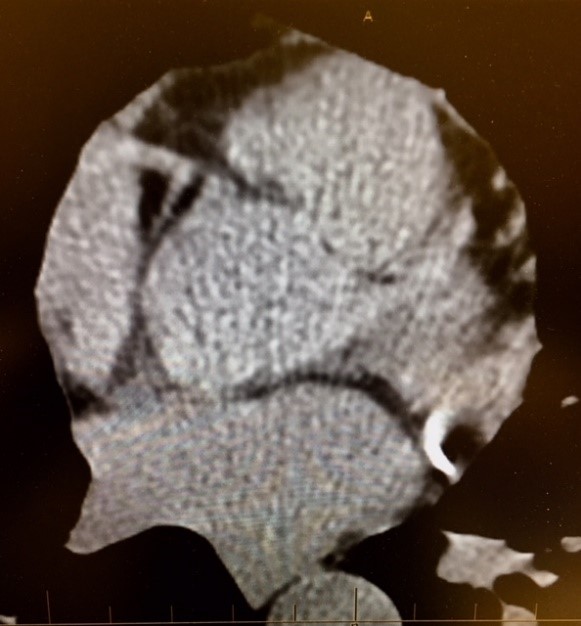

Figures 1-8: Examples of CAC Images

Figure 1: Proximal Left Anterior Descending Artery calcification demonstrated. The calcium score for this artery alone was 250 per Agaston technique.

Figure 6: Proximal Left Anterior Descending Artery calcification is demonstrated in patient with total CAC score of 700.

Figure 7: Proximal Right Coronary Artery calcification demonstrated in patient with RCA calcium score of 900. Note that the sternum is seen at top of image and spine at the bottom.  There is also a small area of calcified plaque seen in the wall of the descending aorta. The bright white character of the areas connotes the relative high density of the calcifications.

Figure 8: Left Main Coronary Artery arising from the Aorta with a calcified plaque in the proximal Left Anterior Descending Artery. The CAC score for the LAD is 250.